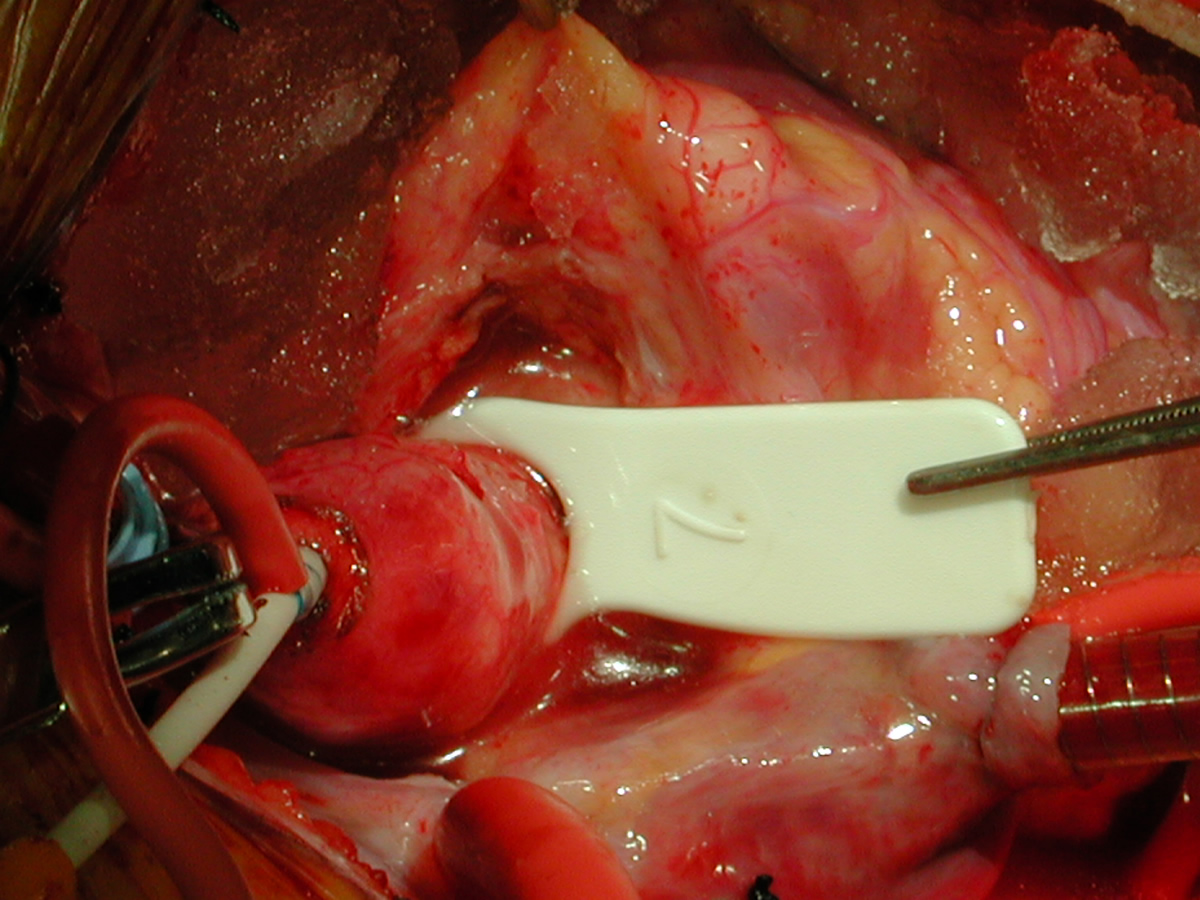

Figures 32 & 33: Shield-shaped homograft patch is being sutured into the incision in the distal ascending aorta to augment the ascending aorta. Figure 34: 16-mm dilator passes easily through reconstructed proximal ascending aorta. This also shows the three complteed patches in the proximal aorta. Figure 35: The same dilator passes into the distal ascending aorta.

Figure Figure Figure Figure